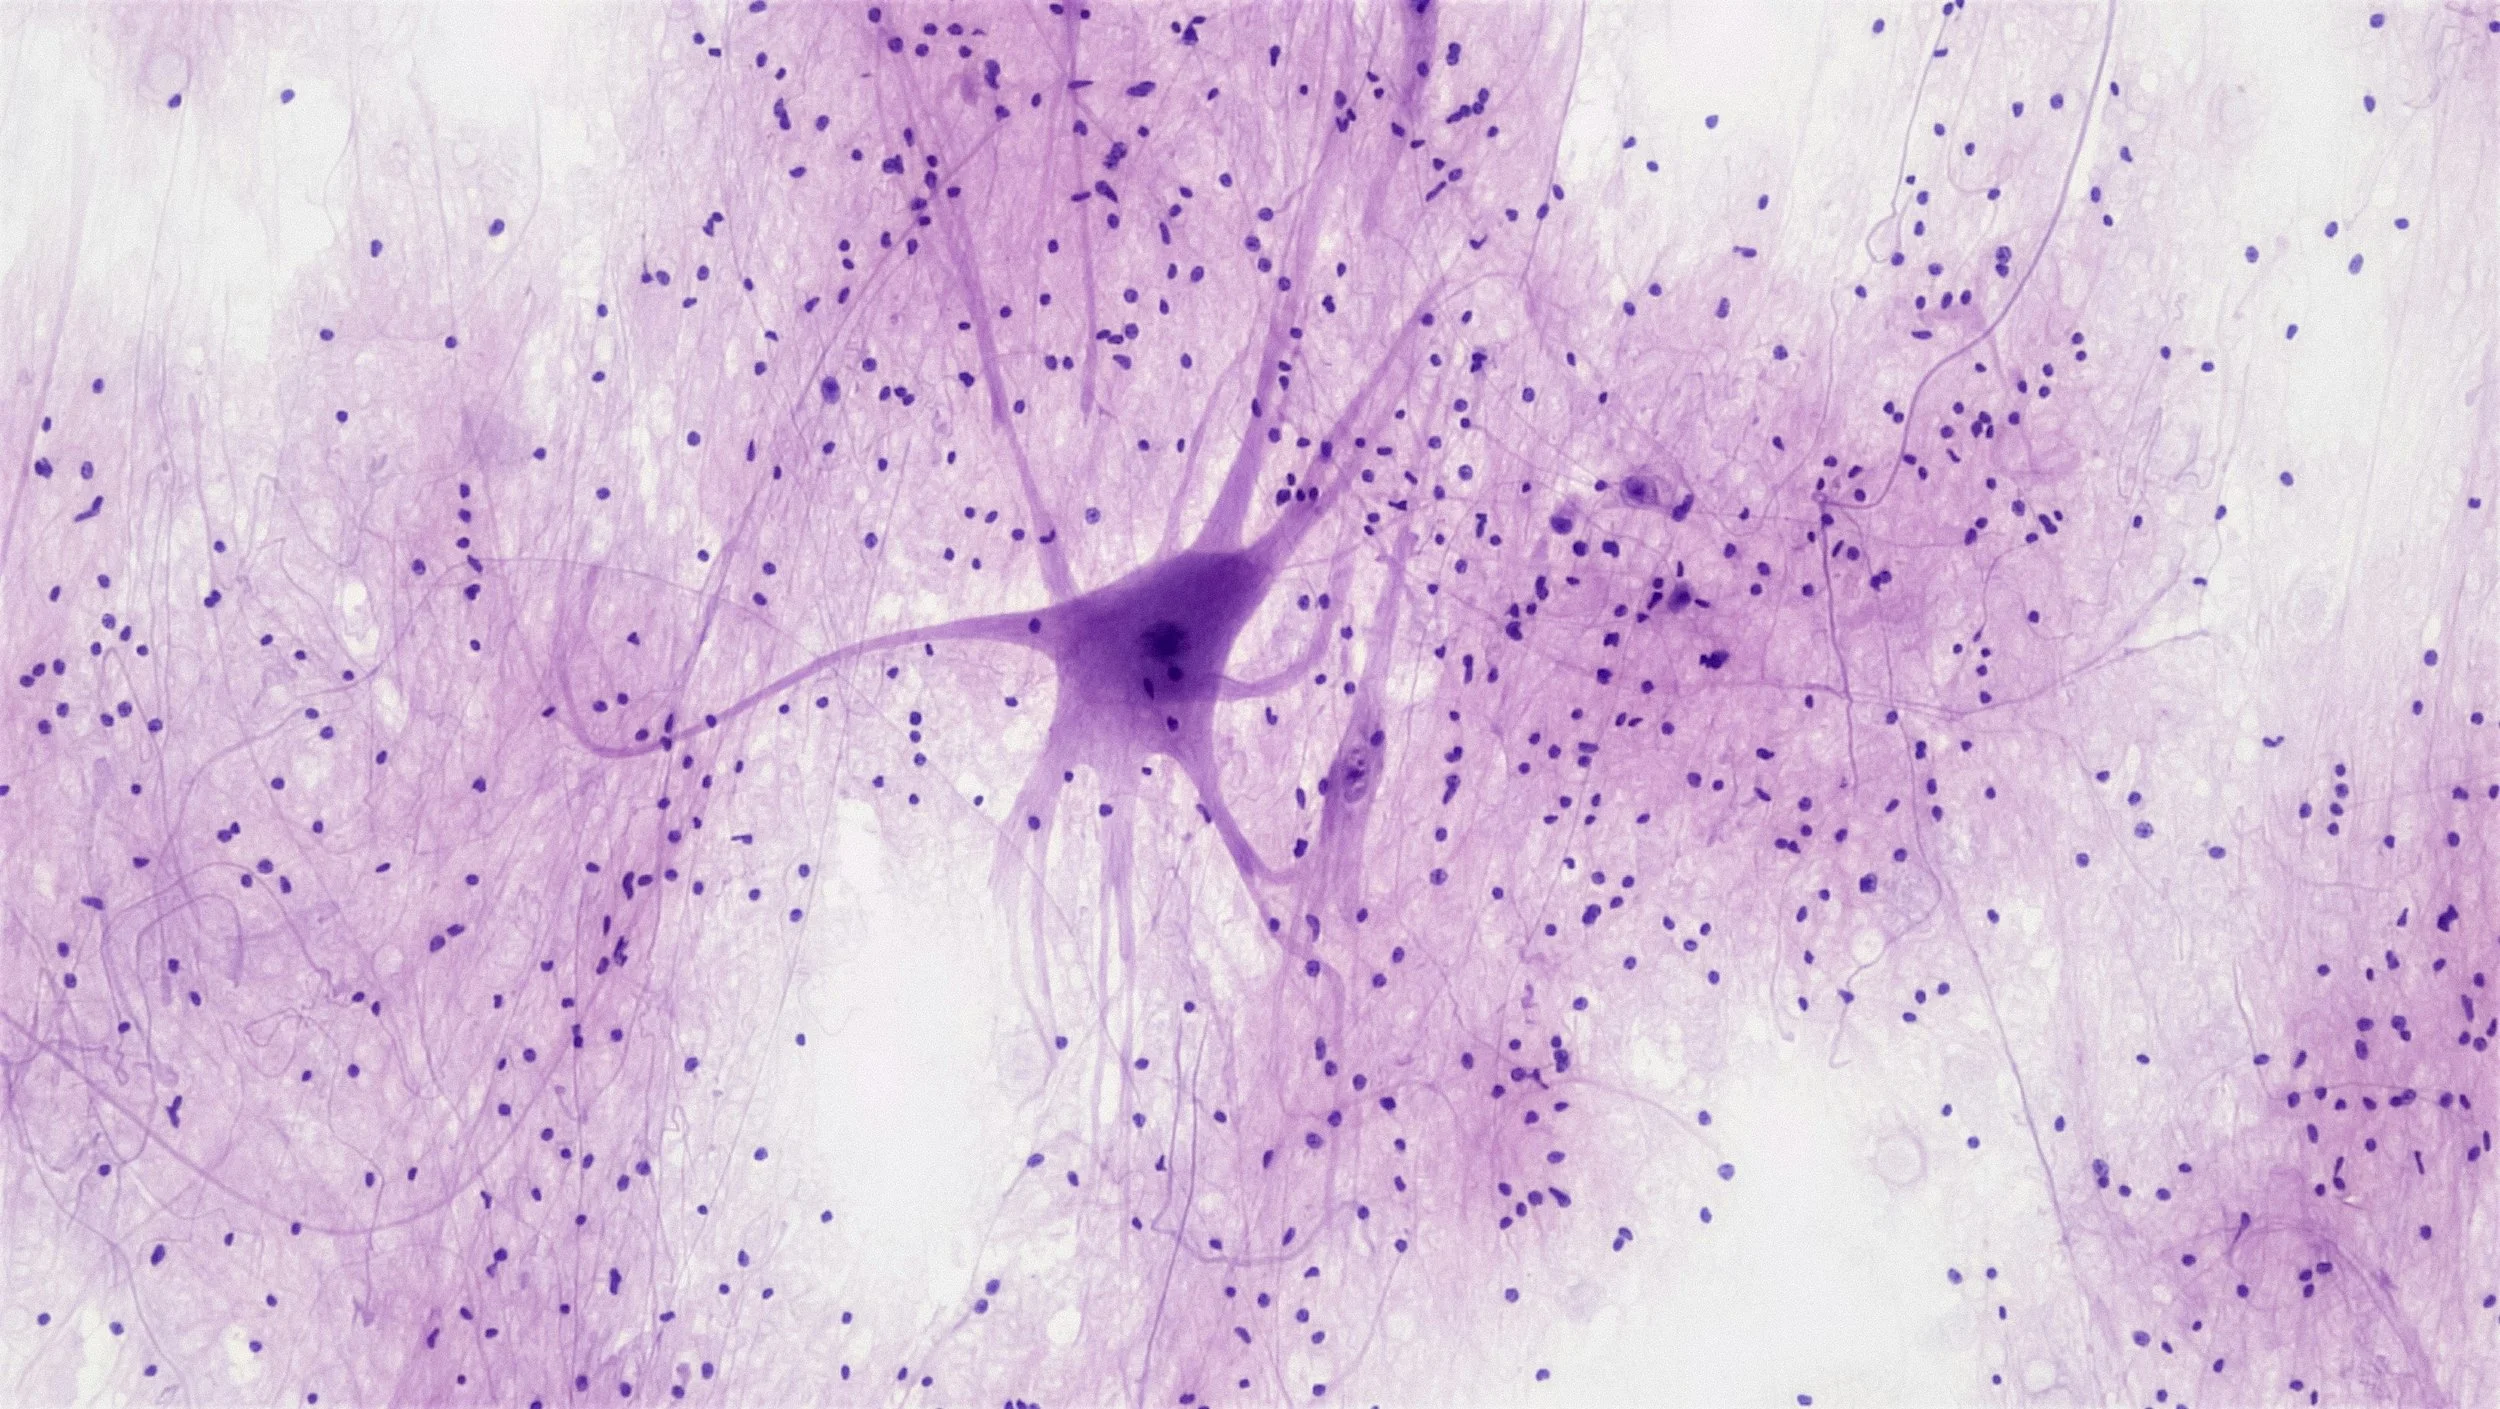

Modeling Macrophages Activation Pattern in X-linked Adrenoleukodystrophy, Metachromatic Leukodystrophy and Adult Onset Leukoencephalopathy With Axonal Spheroids and Pigmented Glia

Combining the science and humanity of microgliopathies.